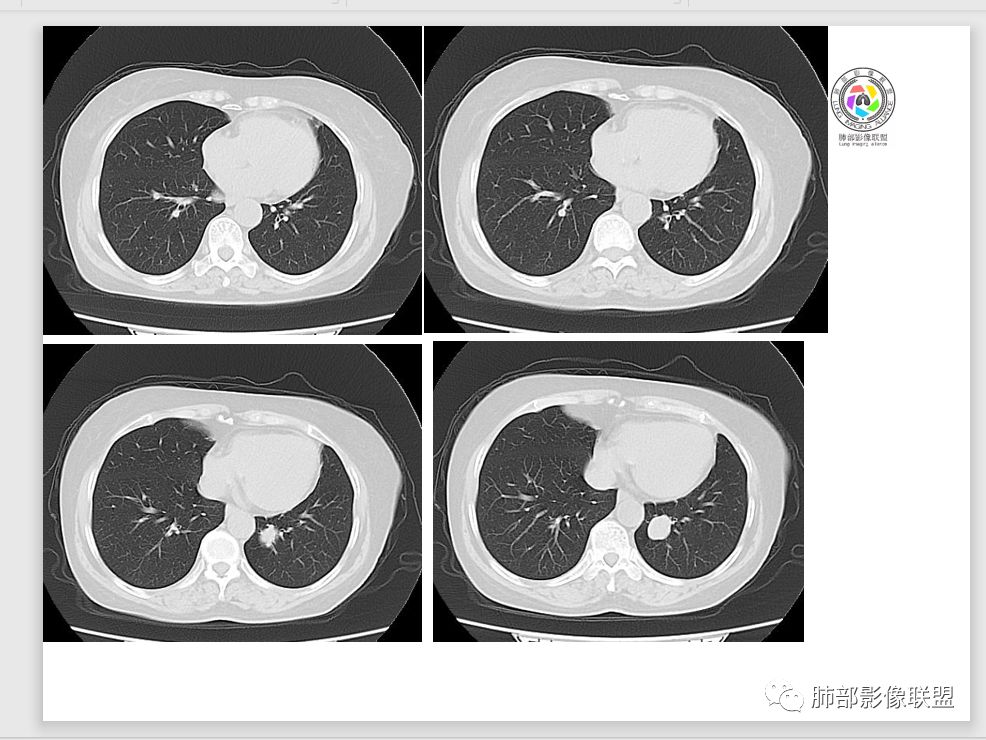

病例资料

Coke with ice:PSP?M-Imaging :良性,PSPShelia:左肺下叶肿块,边缘光整,有血管贴边征,支气管受压推移,延迟强化,考虑PSP?鉴别类癌。不除外恶性

左手:老年女性,无特殊症状,左下肺类圆形结节,边缘清晰,增强见血管贴边,明显强化,无深分叶,无钙化,考虑pspForever:晨读病例病变与血管关系密切 确实psp首先考虑,类癌,腺癌,纤维瘤不能除外没意见:PSP,类癌待排徐超:psp

支气管无关,圆形,光滑,贴别血管稍粗,磨玻璃晕(出血),强化中度,支气管旁疑推挤非阻塞……良性

目前大家意见一致一米阳光:左肺下叶类圆形病灶,边缘清晰,密度均匀,无分叶毛刺等恶性征像,增强,病变明显强化,血管贴边支持PSP,鉴别类癌,后者弱强化,貌似有分叶南边:

1.肺内如此大小的周边较光滑的孤立结节影或块影,密度较均匀的,一般会想到硬化性肺细胞瘤、错构瘤、小细胞癌、大细胞癌、类癌,以及单发转移灶等。

2.边缘光整,坏死不明显,未显示阻塞性炎症或不张,女性患者,肺鳞癌不支持。

3.缺乏典型深分叶及毛刺,强化不显著,似乎也缺乏肺腺癌的影像学特点。

4.未见脂质密度及钙化,强化程度等均不支持错构瘤。

5.同样病灶轻到中度强化也不支持类癌及大多数的硬化性肺细胞瘤(血管瘤样区为主)。

后者不能排除,毕竟不是所有的硬化性肺细胞瘤强化都那么显著。

6.转移瘤缺乏相关临床支持。

7.病灶的形态及强化程度都不能排除小细胞癌及大细胞癌,纵隔尤其是隆凸下未见增大淋巴结似乎不符合小细胞癌等的生物学行为。